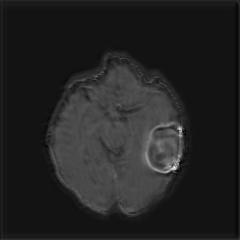

(a) (b) (c) (d)

Boundary Stream:

Fig. 2 demonstrates the output of each of the attention layers in our dedicated boundary stream. In essence, each attention layer progressively localizes the tumor and refines the boundaries. The first attention layer has learned rough estimate of the boundaries around the tumor and localized it, whereas the second and third layers have learned more fine-grained details of the edges and boundaries, refining the localization. Moreover, since our architecture leverages a dilated spatial pyramid pooling to merge the learned feature maps of the regular segmentation stream and the boundary stream, multiscale regional and boundary information have been preserved and fused properly, which has enabled our network to capture the small structural details of the tumor.

(a) (b) (c) (d) (e)